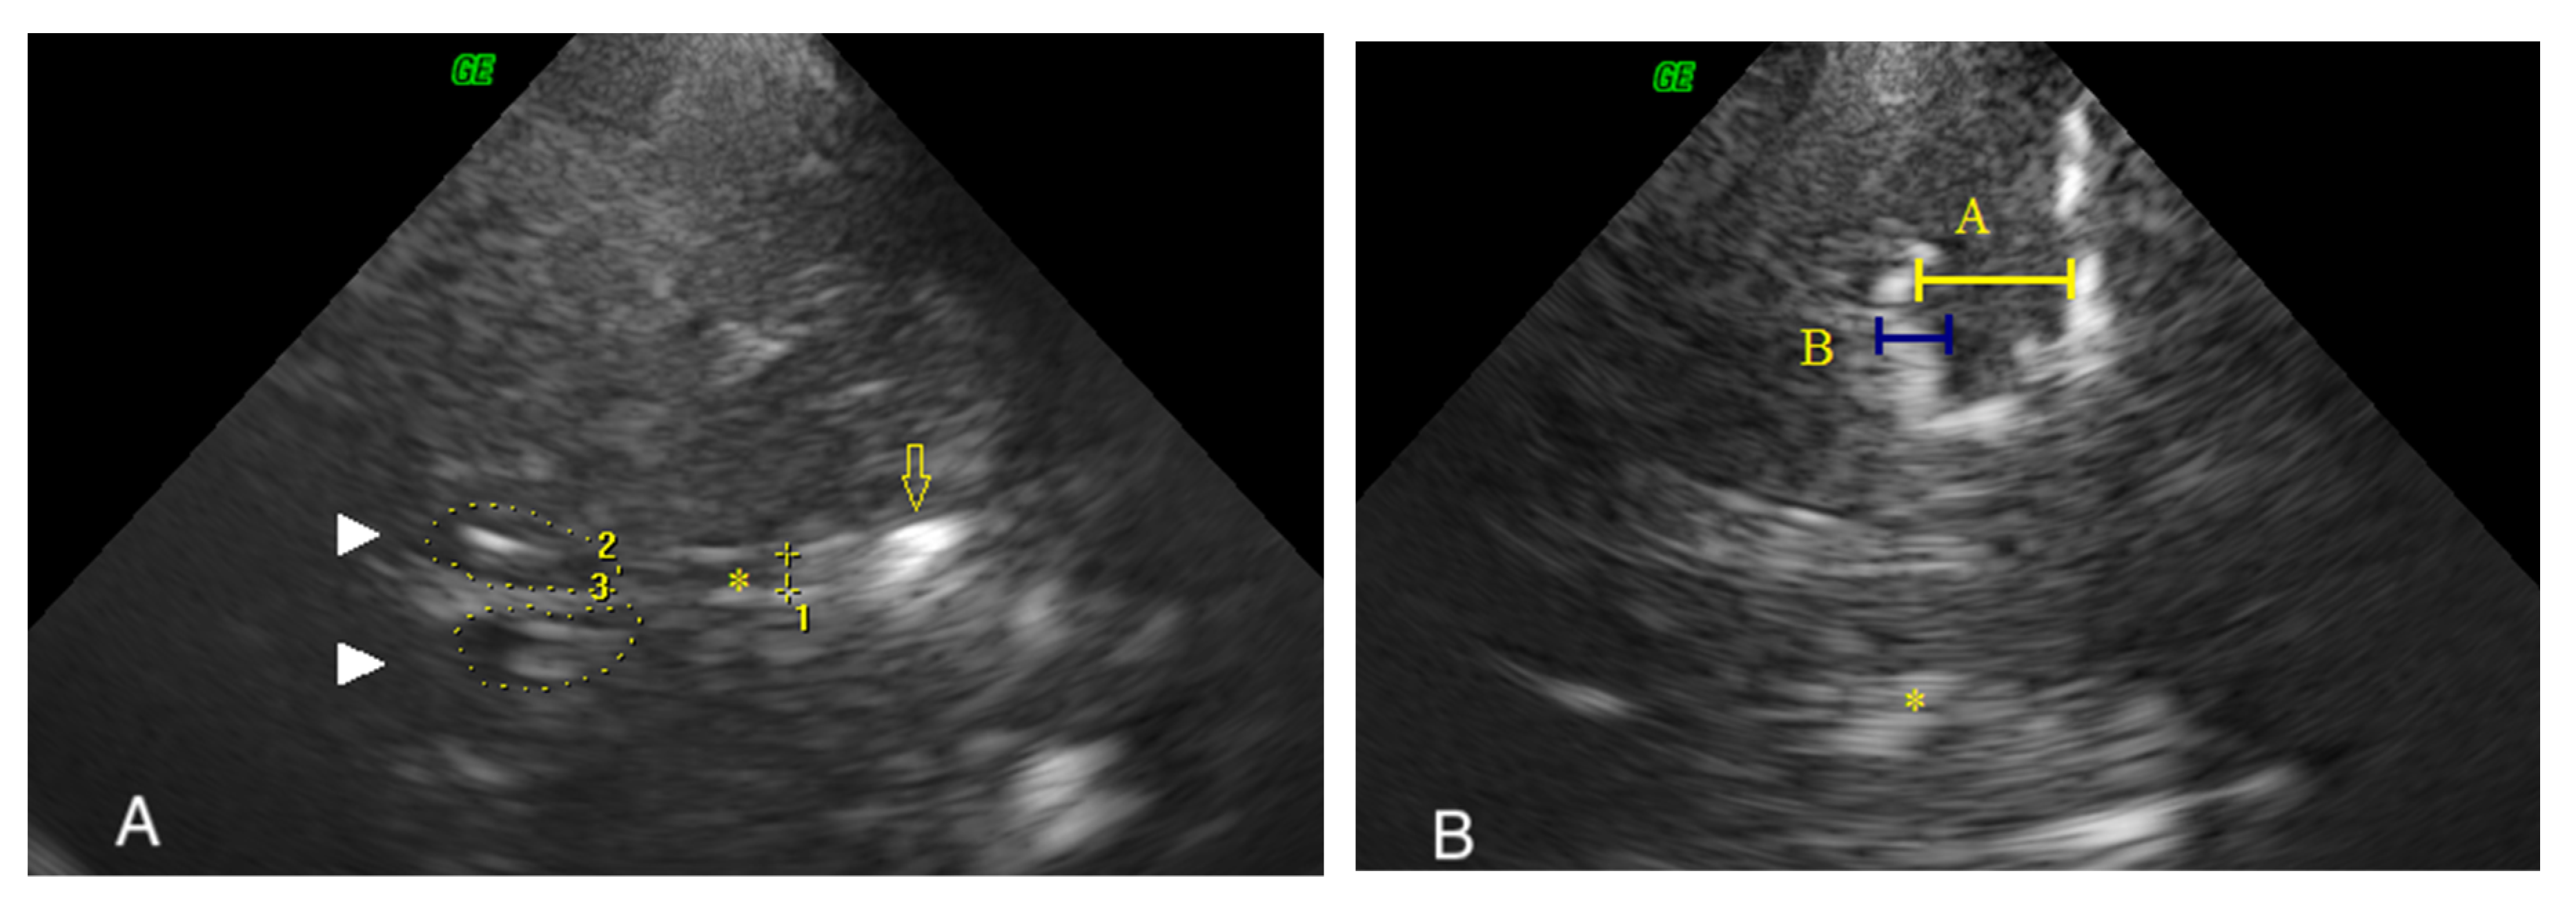

| Height of the MTL (A), mm | 12.9 (2.4) | 14.5 (2.9) | 0.227 | 10.7 (4.8) | 13.8 (3.2) | 0.018 |

| Height of the choroidal fissure (B), mm | 7.0 (2.7) | 6.5 (2.4) | 0.718 | 7.3 (3.0) | 7.3 (1.9) | 0.758 |

| A/B ratio | 1.8 (0.7) | 1.9 (0.6) | 0.383 | 1.5 (0.7) | 1.9 (0.5) | 0.03 |